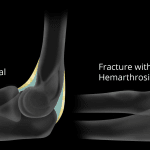

- Acute mildly impacted radial head fracture

- Elbow joint effusion

- Radial head fracture

Acute mildly impacted radial head fracture.

Elbow joint effusion.

- Just like supracondylar fractures, these can be subtle, with an elbow joint effusion sometimes being the only radiographic finding